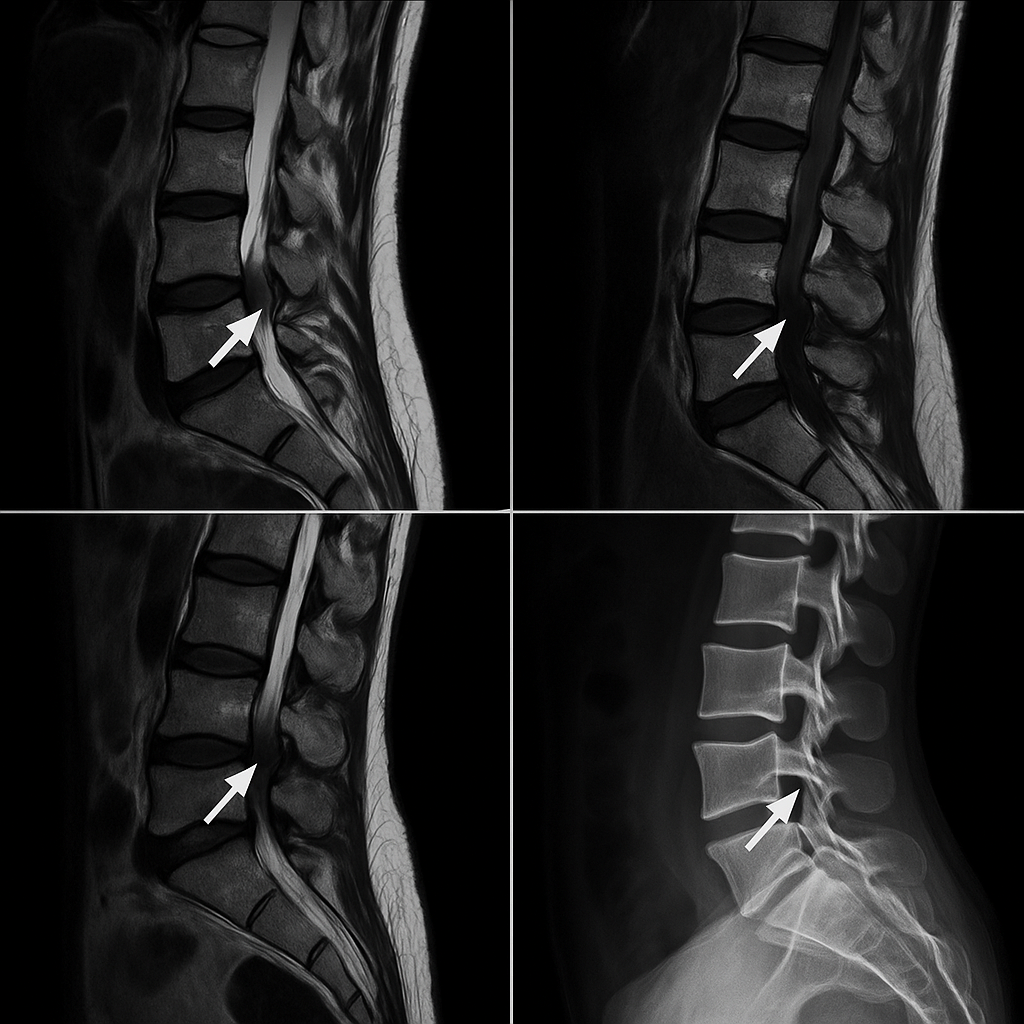

La discopatía degenerativa es un término médico que se refiere al desgaste de los discos intervertebrales, los cuales actúan como amortiguadores entre las vértebras de la columna. Estos discos pierden su elasticidad y altura a medida que envejecemos, lo que puede llevar a la aparición de dolores crónicos, compresión de nervios y otros problemas asociados.

2. Discopatía degenerativa lumbar: Afecta la parte baja de la espalda (columna lumbar) y puede causar dolor lumbar persistente, dificultad para moverse, y síntomas como debilidad o entumecimiento en las piernas.